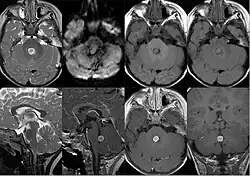

Plexuspapillom im vierten Ventrikel in der Magnetresonanztomographie in verschiedenen Wichtungen und Ebenen.

In der Kernspintomographie stellen sich Plexuspapillome recht charakteristisch als intensiv homogen Kontrastmittel aufnehmende, in den Hirnventrikeln gelegene Masse mit blumenkohlartiger Form dar. Bei Kindern und Jugendlichen sind vor allem die Seitenventrikel betroffen, bei Erwachsenen gleichermaßen der vierte Ventrikel. Selten können Plexuspapillome auch im dritten Ventrikel oder ganz außerhalb des Ventrikelsystems liegen.[1][8]